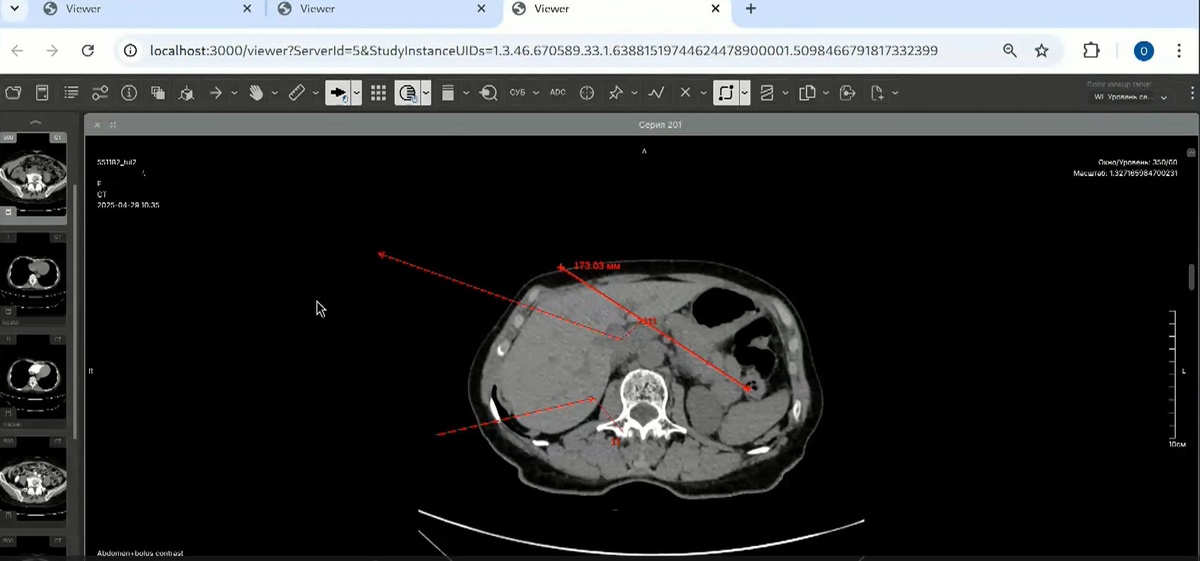

Сегодня мы хотим провести небольшую демонстрацию продукта — веб-просмотрщика медицинских изображений. Этот просмотрщик отличается от большинства аналогов тем, что он построен на веб-технологиях. Вы можете просматривать медицинские изображения, не устанавливая дополнительное программное обеспечение, просто перейдя по ссылке. Предлагаем посмотреть одно из изображений из хранилища медицинских снимков в разных режимах. Данный проект был разработан для клиентов, и мы продемонстрировали, что глубоко погрузились в тему 3D-визуализации медицинских изображений. Мы можем создать подобный продукт или что-то, где используются 3D-технологии, например, в неразрушающем контроле или визуализации на производстве. Мы знаем, как оптимизировать все эти процессы и какие открытые решения стоит использовать. Мы имеем опыт разработки продуктов с нуля и знаем, какие подводные камни существуют у различных open-source решений. Браузерные технологии являются специфичными, но мы знаем, как с ними работать.

• Просмотр изображений: Демонстрация плавности работы просмотрщика. Можно аннотировать изображения и измерять детали.

2D-режим: простой режим просмотра плоских изображений.